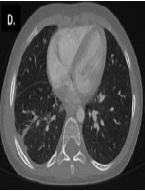

Early Subcutaneous Emphysema Following Arthroscopy: A Case Report

M.G. Di Salvatore, R. Pezzella*, V. Calvisi